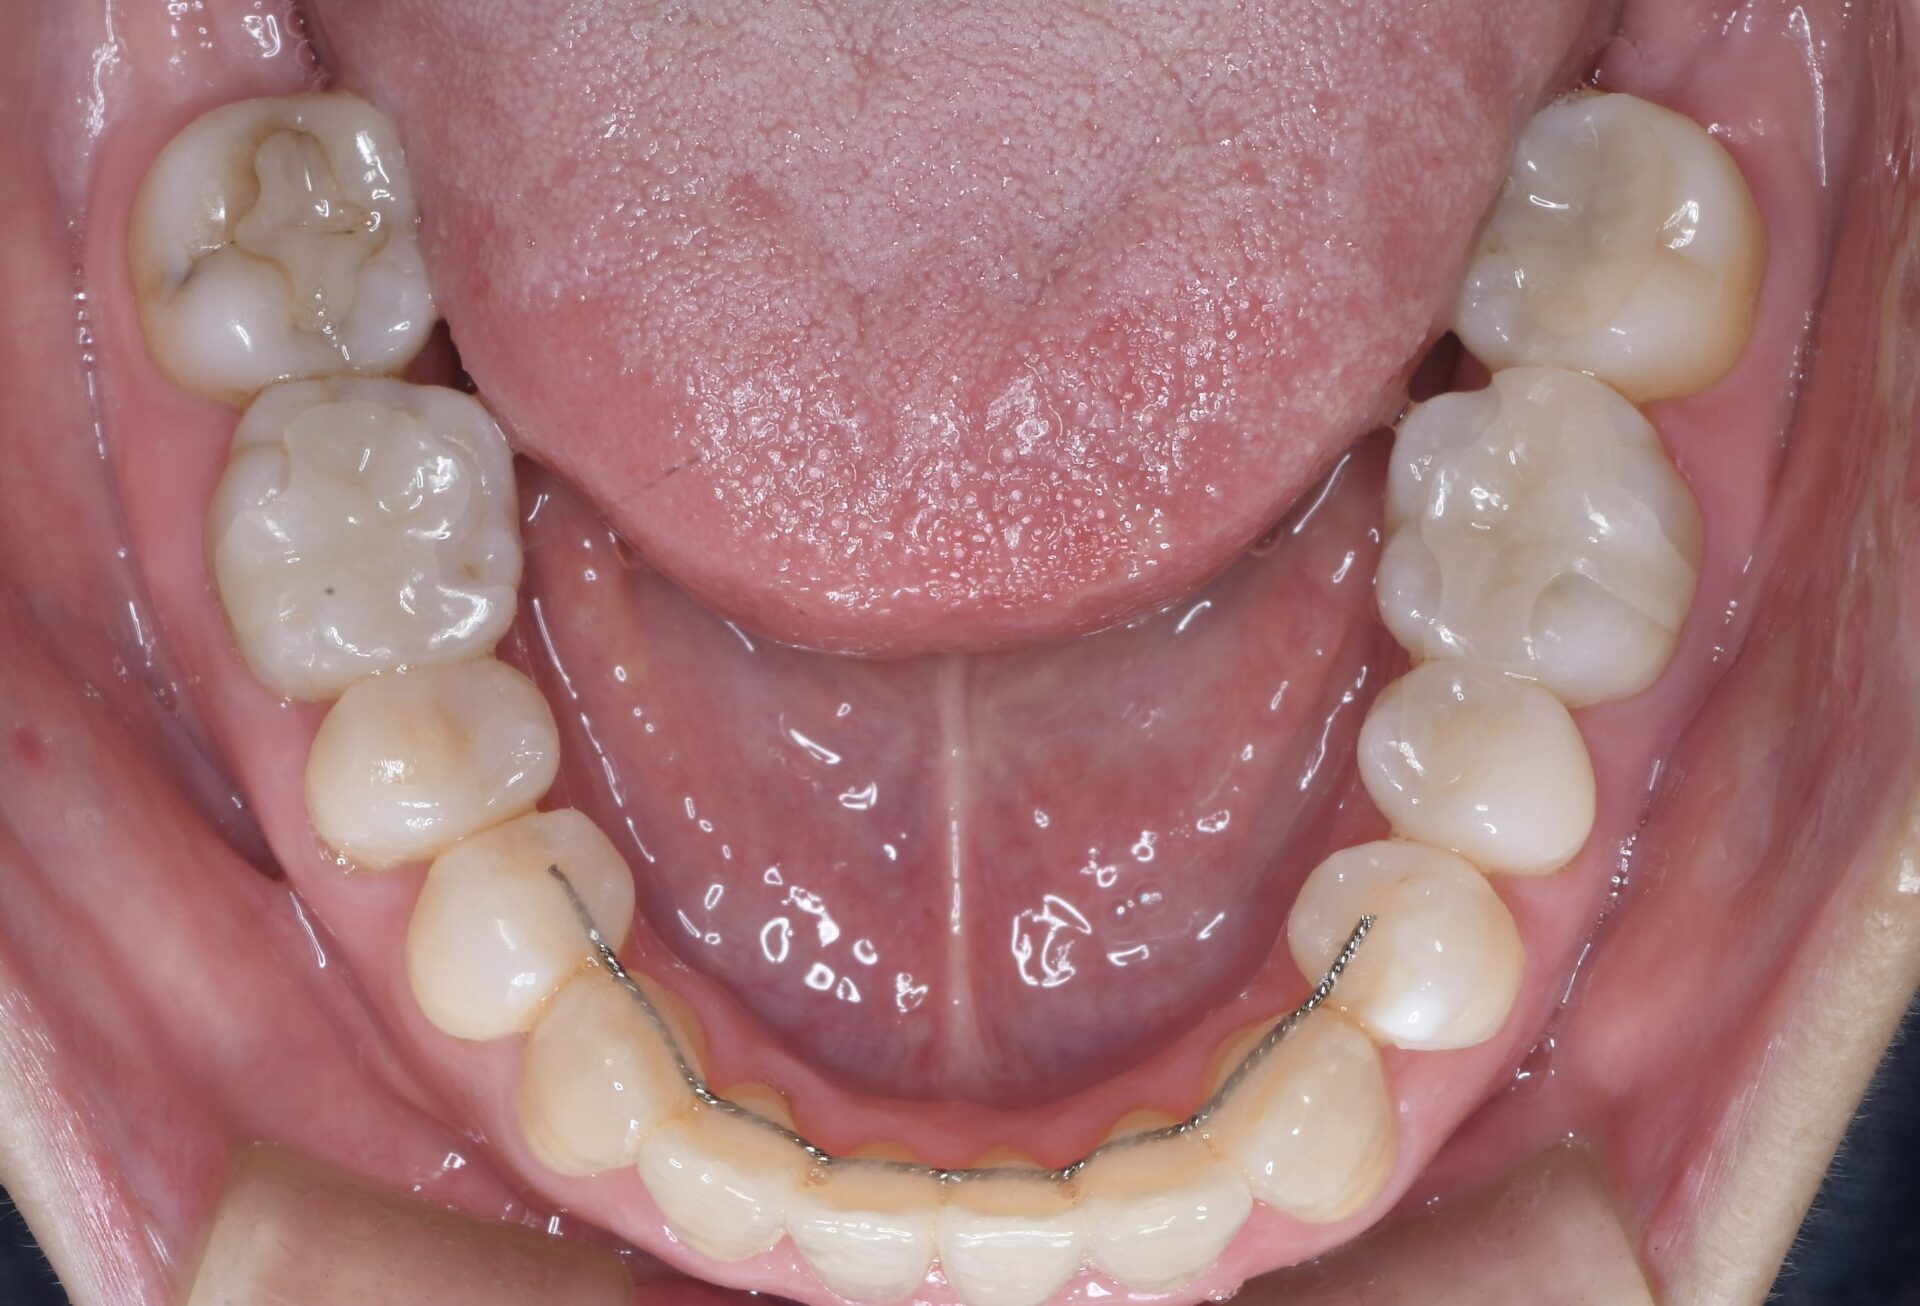

矯正治療スタート時(上顎)

メインテナンス時(上顎)